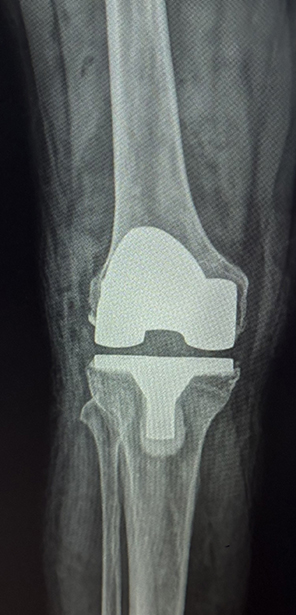

Figure 2. AP radiograph after total knee arthroplasty

Courtesy of Douglas W. Lundy, MD, MBA, FAAOS

One of the main obstacles in developing an arthroplasty program in resource-challenged countries is the sustainable availability of implants. Finding inexpensive components that would remain available for the foreseeable future was critical to the project. Local surgeons might struggle to keep up with the different techniques and specific implant nuances if cost demanded switching between implant manufacturers. The local host, Annelise Olson, MD, was able to identify an inexpensive implant source anticipated to support the arthroplasty program in CEML for quite a while. Though far less expensive than the implants used in the United States, these components are of good quality, and the tibial inserts are composed of ultra-high molecular weight polyethylene.